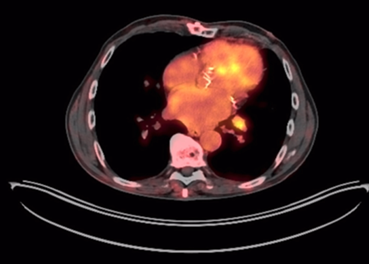

One year later, a follow-up PET-CT scan showed a decrease in the size and metabolism of cervical lymph nodes; however, a pulmonary nodule was present in the left lower lobe (13 mm), along with left hilar lymphadenopathy (12 mm), findings consistent with systemic tumor progression (Figure 2).

Figure 2

Thoracic PET-CT. Left hilar lymphadenopathy measuring 12 mm, hypermetabolic (SUV LBM 3), suggestive of metastatic origin.

2661-6653-onco-35-03-26-gf2.png

Source: SOLCA Intranet - Guayaquil.